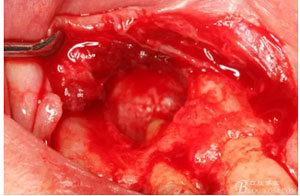

圖12.摘除的12根尖區(qū)的囊壁組織。

圖13.囊壁摘除后形成的骨腔,12牙根完全裸露在骨腔內(nèi)。